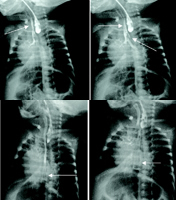

最常見為Ⅲ型,約占85%~93%。本例為Ⅳ型,比較罕見。食管閉鎖的典型臨床表現為生後餵奶後嗆咳,同時出現呼吸困難及面色發紺。患兒有唾液過多,可見帶泡沫的唾液從口腔、鼻孔溢出。當懷疑食管閉鎖時,經鼻孔或口腔插入胃管,正常小兒可順利進入胃內,而食管閉鎖患兒插管約8~12 cm即受阻,或導管屢次從口腔翻出,X線檢查能明確診斷。經導管注入1 ml造影劑即可顯示食管上段的盲袋及其位置。第Ⅳ型表現為食管上段盲端有碘劑流入氣管內,同時胃腸內充氣,造影劑可經氣管入另一瘺口至食管遠端。